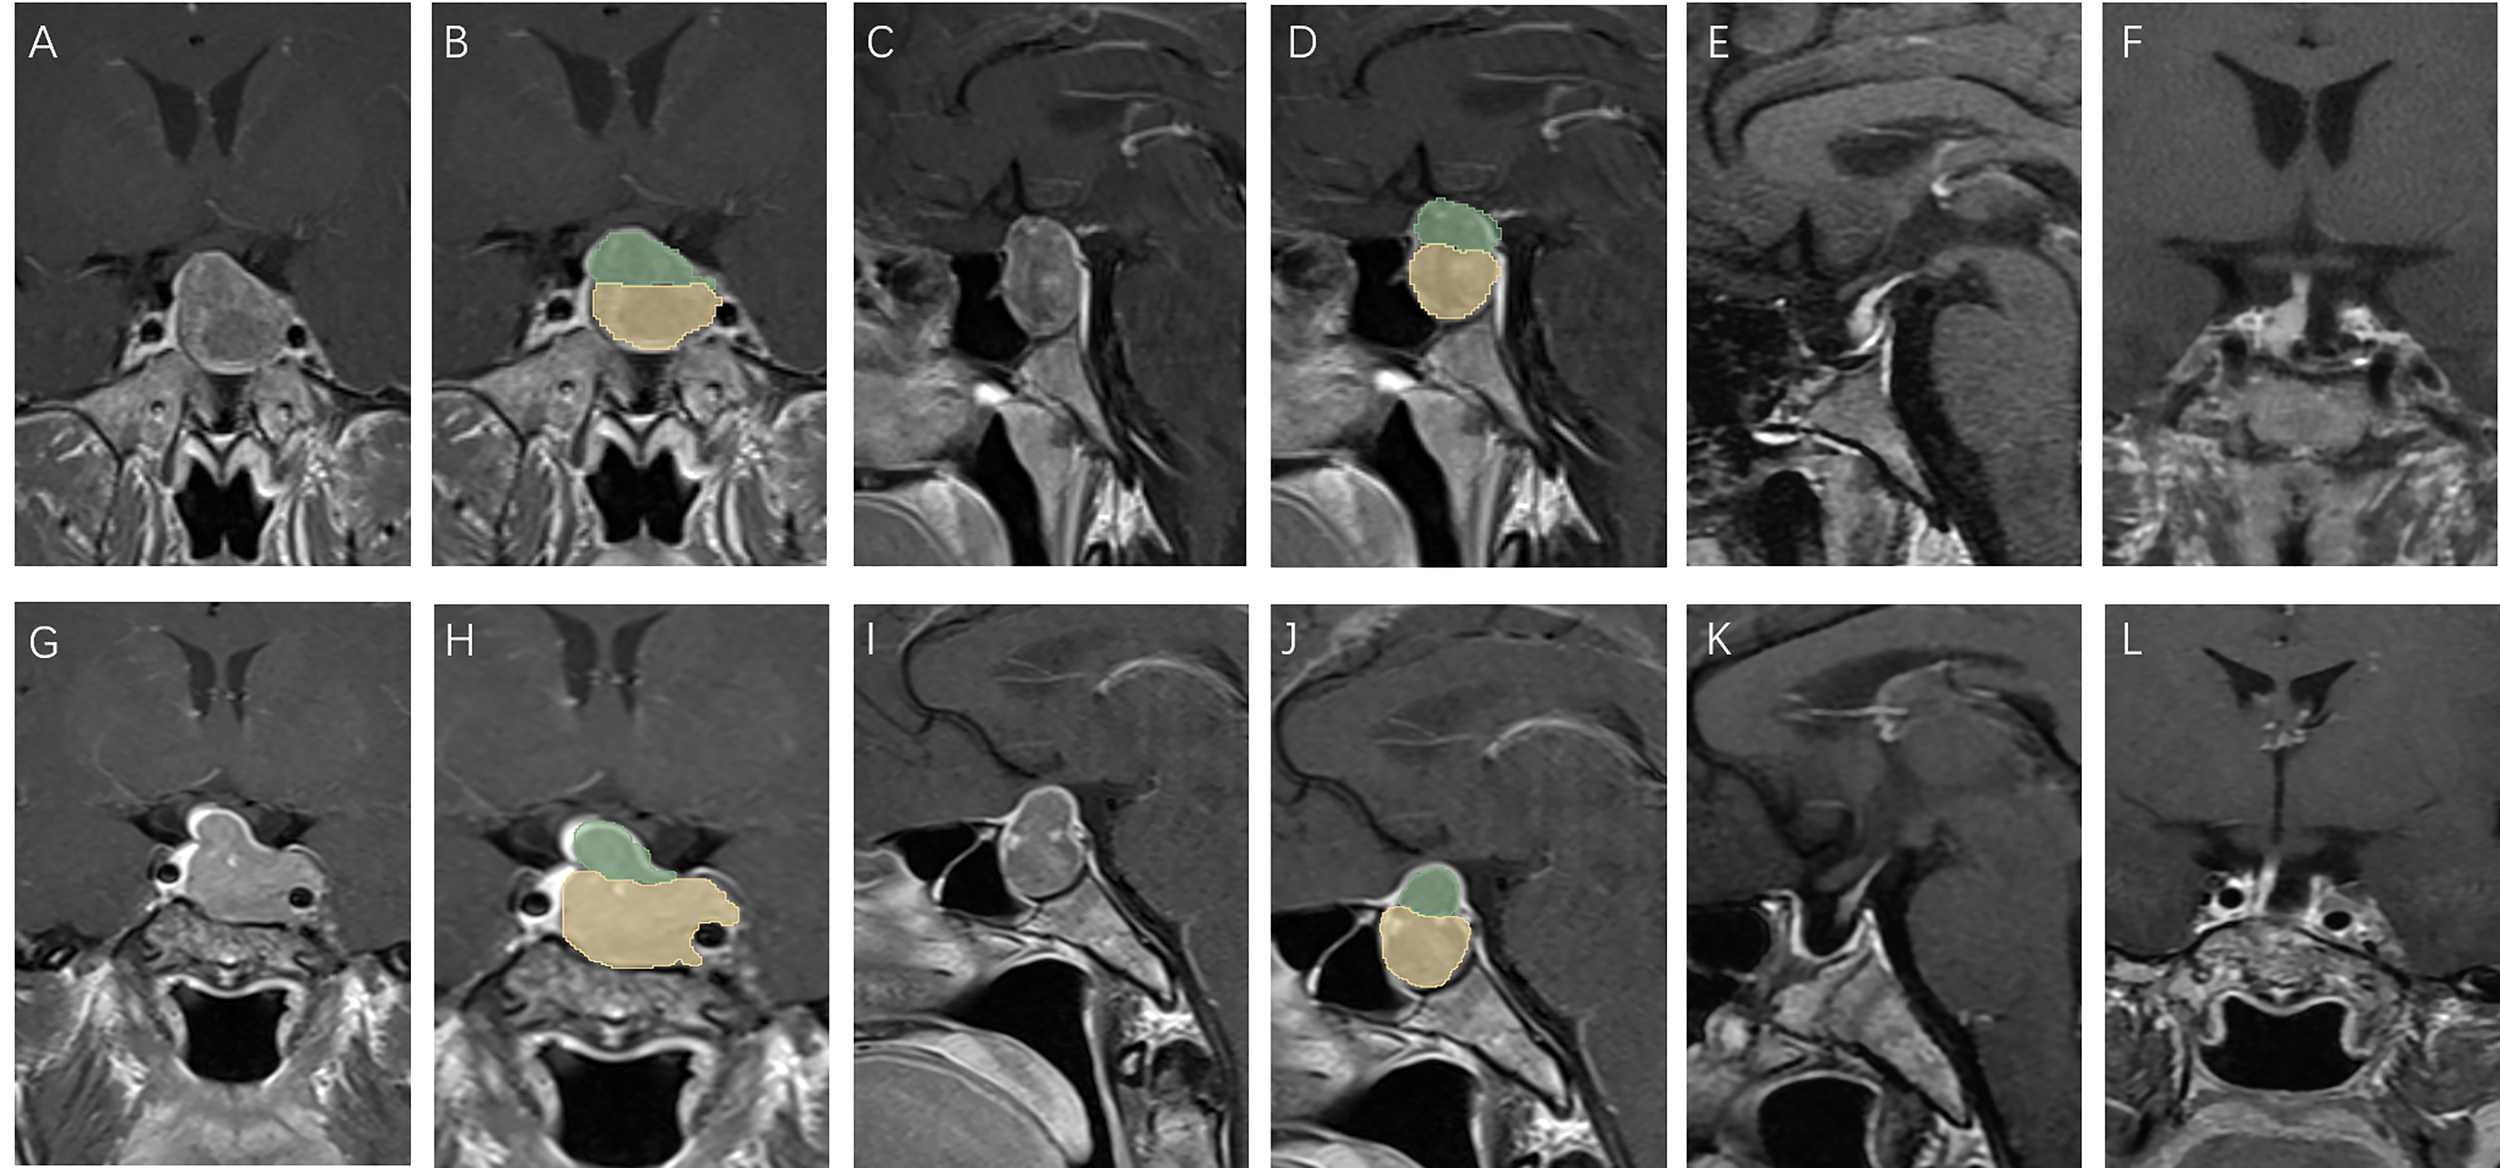

Patients with high V-D value: A 51 year old female, TV: 13699.48 mm3, V2: 1620.19 mm3, V1:12079.29 mm3, V-D: 8.64 (A–D), relapse 13 months after surgery (E, F); a 30 year old female, TV: 470.46 mm3, V2: 186.48 mm3, V1:283.98 mm3, V-D: 2.56 (G–J), relapse 94 months after surgery (K, L).

Figure 4

Patients with low V-D value: A 39 year old male, TV: 5781.19 mm3, V2: 4376.40 mm3, V1:1404.79 mm3, V-D: 1.19 (A–D), no relapse in 7 years of follow-up (E, F); a 43 year old female, TV: 5888.45 mm3, V2: 5188.17 mm3, V1:700.28 mm3, V-D: 1.31 (G–J), no relapse in 7 years of follow-up (K, L).

Some studies have used molecular markers for the prediction of recurrence (15). However, pathology results can only be obtained after surgery, and few factors can predict recurrence before surgery. Predicting recurrence before surgery is essential not only for reducing patients’ distress but also for providing individual advice for their treatment. If a high potential of recurrence in a patient can be detected before surgery, a more aggressive surgery plan could be drawn up, and the follow-up plan adhered to more diligently. We found that a higher V-D value was positively related to tumor recurrence after surgery, showing good efficacy in the prediction of residual tumors (Figures 3, 4). The V-D value can be obtained from preoperative radiological data and used in the preoperative discussion when seeking patient consent. For those with higher V-D values, surgeons can devise more radical strategies, such as resection of the internal wall of the cavernous sinus or extended transsphenoidal surgery. Intraoperative MRI detection can also be performed for those with higher V-D values to provide the greatest chance for achieving total resection.